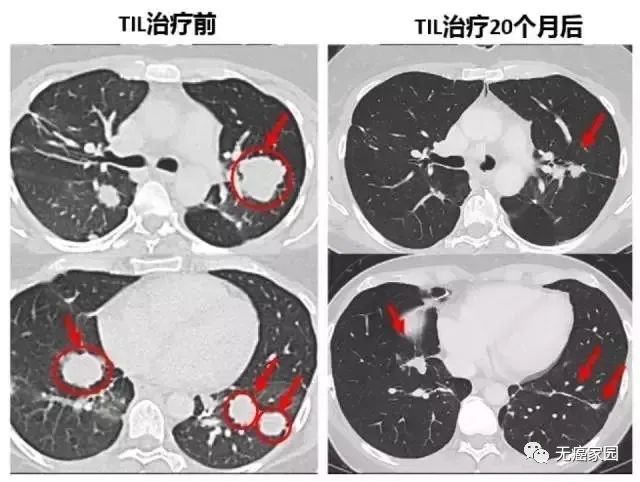

对Melinda发挥巨大作用的是第二次输入的1270亿个免疫细胞,起初她的肿瘤体积缩小60%,待试验结束后,又接受了免疫检查点抑制剂pembrolizumab的治疗,成功地缩小了肿瘤,目前身体任何部位已确保处于无癌状态。

下面的对照图可以非常明显看到,第二次治疗前肺部布满的肿瘤,包括一些个头非常大的,第二次TIL治疗20个月后复查,这些肿瘤都非常显著的缩小了,专家认为这很可能是瘢痕。